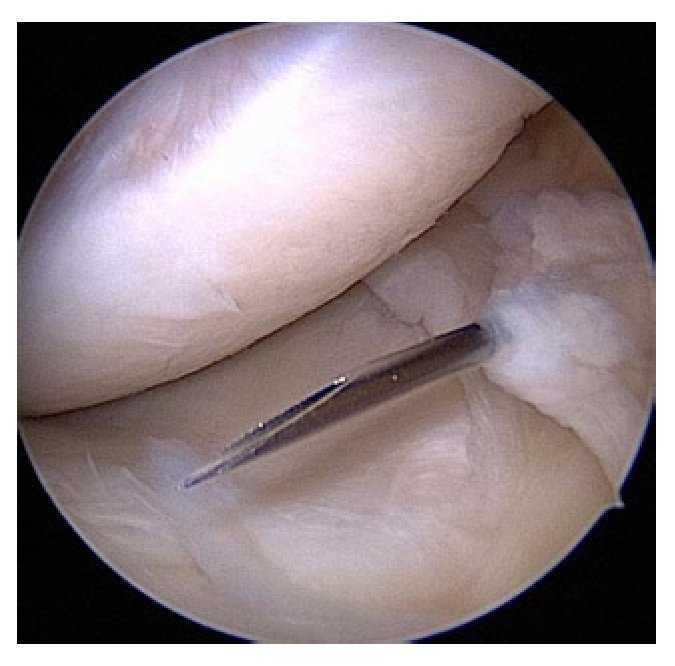

Fig. 12 La guía (a) se introduce en toda su longitud perforando con la broca más delgada (diámetro 4,5 mm) (b). A continuación se mide la longitud del túnel con un medidor de profundidad especial (c). La longitud del túnel varía entre 30 y 45 mm.

Fig. 13 Después de determinar la longitud del túnel se vuelve a insertar la guía dentro del túnel y se ensancha paso a paso a lo largo de los 30 mm distales, hasta conseguir el diámetro del injerto (a). A modo alternativo, también se puede dilatar el túnel con dilatadores femorales (b). Durante el proceso de dilatación, el hueso se comprime en la zona de la pared del túnel. Durante la perforación pueden producirse defectos óseos.